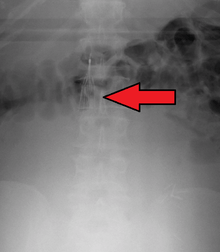

Inferior vena cava filter

Placement

IVC filters are placed endovascularly, meaning that they are inserted via the blood vessels. Historically, IVC filters were placed surgically, but with modern filters that can be compressed into much thinner catheters, access to the venous system can be obtained via the femoral vein (the large vein in the groin), the internal jugular vein (the large vein in the neck) or the arm veins with one design. Choice of route depends mainly on the number and location of any blood clot within the venous system. To place the filter, a catheter is guided into the IVC using fluoroscopic guidance, then the filter is pushed through the catheter and deployed into the desired location, usually just below the junction of the IVC and the lowest renal vein.[39]

Review of prior cross-sectional imaging or a venogram of the IVC is performed before deploying the filter to assess for potential anatomic variations, thrombi within the IVC, or areas of stenoses, as well as to estimate the diameter of the IVC. Rarely, ultrasound-guided placement is preferred in the setting of contrast allergy, renal insufficiency, and when patient immobility is desired. The size of the IVC may affect which filter is deployed, as some (such as the Birds Nest) are approved to accommodate larger cavae. There are situations where the filter is placed above the renal veins (e.g. pregnant patients or women of childbearing age, renal or gonadal vein thromboses, etc.). Also, if there is duplication of the IVC, the filter is placed above the confluence of the two IVCs [40] or a filter can be placed within each IVC.[41]